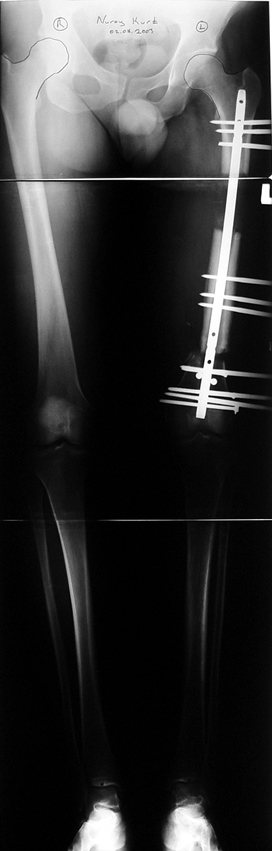

Case 1